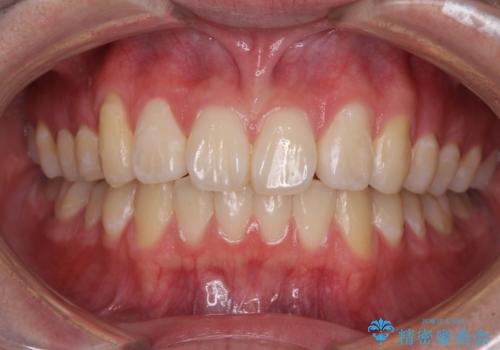

- 八重歯を気にして来院された高校生の患者様です。

ボディーコンタクトの激しい部活動を行っているため、補助装置とインビザラインを用いて、部活動を継続しながら治療を行うこととしました。

八重歯を効率よく改善するため、補助装置を使用して上顎の奥歯を後方に移動させました。

部活動をしながらでしたが、マウスピースをしっかりと装着してくださったので、1年半程度で終了することができました。